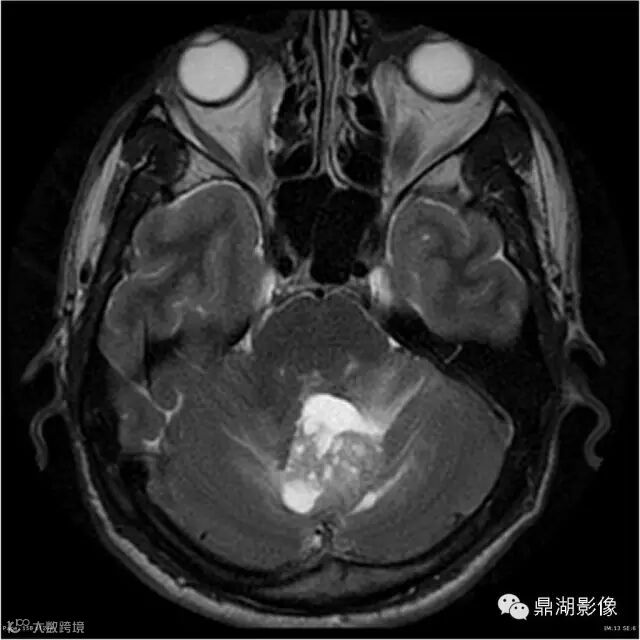

Axial T2WI

影像:可见一个约43 x 36 x 31mm的从小脑蚓部延伸而来的占位,T1WI、T2WI呈高低混杂信号,病灶周边见流空血管影及水肿带,增强病灶明显强化,中心见无明显坏死区,它紧靠左小脑幕上。第四脑室受压变窄,室管膜水肿,可见脑桥及延脑扁桃体进入枕骨大孔。

本例为一例实质性血管母细胞瘤。实性血管母细胞瘤CT平扫示病灶呈等或高密度,增强后可见明显强化。MRI平扫通常病灶很不均质,T1呈稍低信号为主的较混杂信号,T2呈等、高信号,DWI通常呈低信号或等信号。文献报道,实性血管母细胞瘤较典型的表现为瘤内及瘤周扩张的流空血管影,瘤周中、重度水肿。因此,小脑半球区的单发肿块伴流空血管影,周围大片水肿以及增强后肿块明显强化"形态规则"边界清楚,此时应将实性血管母细胞瘤考虑在内。